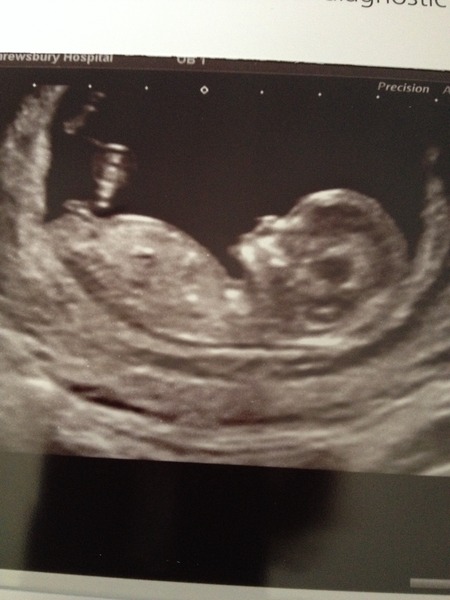

juniper i would have guessed boy - but a) i am guessing nd b) not sure i believe in skull theory. Here's my little she-Bean. She apparently has a girlie head! I need to find my scans from my boys - when i finally move into the new house i can dig them out - 9 days until we get the keys, 12 days until moving day Grin

I've posted this pic before but I just love showing the little fella off! I'm not sure I believe the skull theory as his skull looks very similar in shape to some of the pics that have been posted of girls?